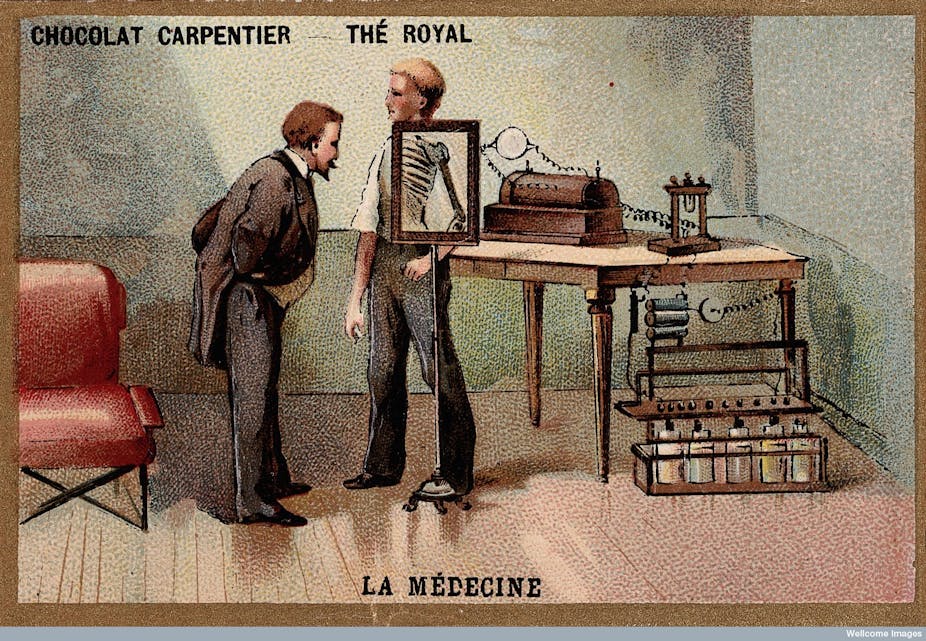

Almost immediately after the discovery of the new rays, scientists and physicians began using them to peer inside the body without cutting it open, revealing not only normal structures but also fractures, pneumonias and even foreign objects, such as swallowed coins.